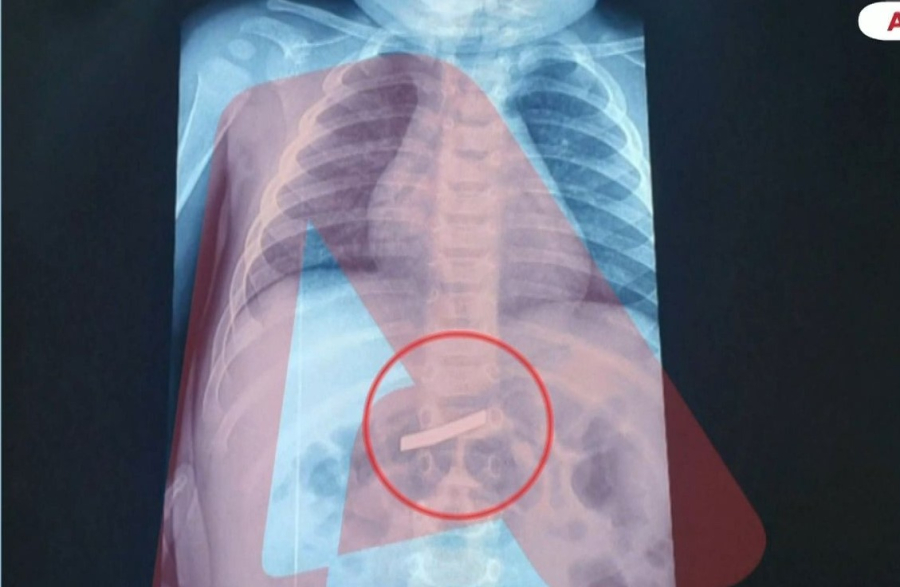

Οι γιατροί έκαναν ακτινογραφίες στο τρίχρονο, ώστε να εντοπίσουν με ακρίβεια τη θέση του επικίνδυνου αντικειμένου στο σώμα του. Στη συνέχεια κρίθηκε απαραίτητη η χειρουργική επέμβαση, η οποία πραγματοποιήθηκε επιτυχώς.